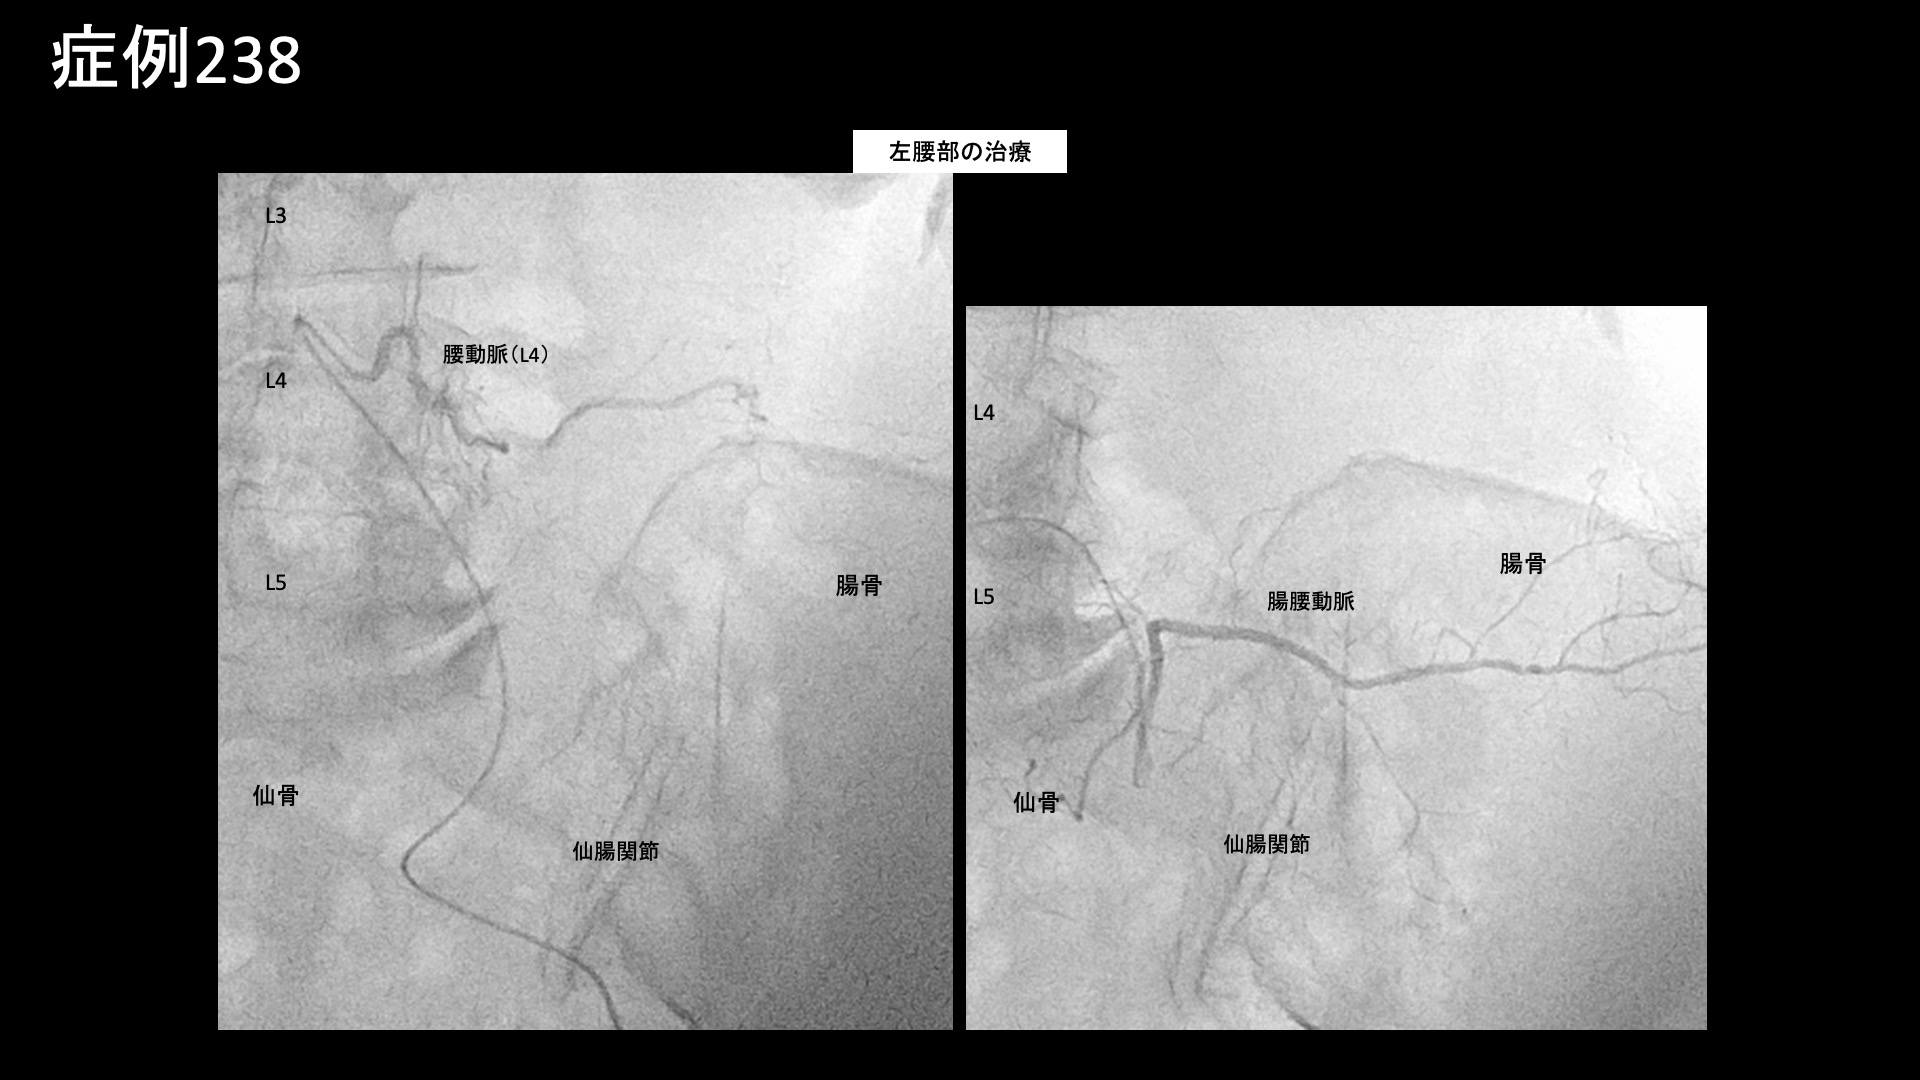

腰:椎間関節炎など 【80代:女性】新型コロナウイルス感染を契機に悪化した変形性腰椎症による腰痛/坐骨神経痛(新型コロナウイルス感染、変形性腰椎症、腰痛、坐骨神経痛) 2025.09.19 鴨井院長による動画解説 受診までの経過 20年前にゴルフ中に腰を痛めて以来、慢性的に腰痛を繰り返すようになりました。坐骨神経痛と診断され、ブロック注射などの治療を受けてきました。5年前から悪化してきましたが、新型コロナウイルスに感染したことをきっかけに痛みがさらに激しくなりました。ブロック注射も効かなくなってしまいました。仰向けで寝る分には痛みはない一方で、立位や歩行時に、特に左側の痛み・しびれが辛く感じていました。 診察時の所見 レントゲンでは一見して高度の腰椎変形を認め、歩くのもままならないくらいのもっと強い症状が出ていても不思議ではないくらいでした。腰の動きを確認すると、前屈で疼痛が誘発され、全ての動作において中等度以上の可動域制限がみられました。股関節の動きは保たれていました。後上腸骨棘では比較的強い圧痛が認められました。その他の診察所見と併せて、左坐骨神経痛を伴った変形性腰椎症、仙腸関節障害と診断しました。構造的異常は強いものの、神経障害としては固定化されておらず治療による一定の改善が期待されました。治療適応と判断し、モヤモヤ血管(病的新生血管)に対する運動器カテーテル治療(微細動脈塞栓術)を受けていただきました。 治療の所見 腰椎レベル~股関節周囲レベルにかけて広範囲の治療を行いました。左腰動脈、腸腰動脈などで特に再現痛を認めました。 *再現痛とは、薬液投与時に普段の痛みが一定程度再現される現象です。責任血管の同定のための参考とします。特に腰臀部領域では、モヤモヤ血管を視認することが困難なことが多いため再現痛の確認は重要です。 治療後の経過 治療後3-4日はとても楽でしたが、その後再燃し、午前中は楽に感じるものの、治療後2週間ではまだ大きく変わりはありませんでした。治療後1ヶ月、鼠径部に感じていた痛みは無くなりました。歩く時の痛みについてはまだ一部の改善にとどまっていました。治療後2ヶ月、入室時のご様子から既にこれまでと違っていて、歩容が改善してスムーズに入室されました。強い痛みは半減し、立ち上がりの際には痛むものの、歩いている内に無くなるようになりました。寝がえりの際の痛みも無くなりました。治療後2ヶ月半を過ぎる頃から、左側の痛みはほとんど無くなってきました。治療後5ヶ月時点でも痛みなく良い状態を維持できています。本症例では、長年くすぶり続けた慢性炎症が新型コロナウイルス感染を機に悪化したことが考えられました。高度の腰椎変形があり治療の有効性に懸念がありましたが、カテーテル治療は『強い炎症にはよく効く』という側面があります。感染を契機に悪化した症状には有効な可能性が高いです。 坐骨神経痛の詳しい病状説明はこちら 【90代:女性】ここにできたら要注意!超高齢者に生じた頭部・顔面の帯状疱疹後神経痛(発症1ヶ月) (帯状疱疹後神経痛) 前の記事 【70代:男性】夜間痛がその日のうちに改善!強い炎症を伴った変形性膝関節症に対する運動器カテーテル治療(変形性膝関節症) 次の記事